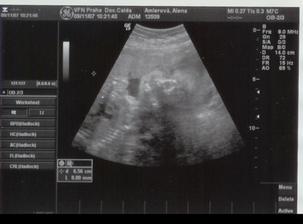

21.11.2007 jsme byly na 3D,4D UTZ mame cca 1296g a malá vůbec nespolupracovala proste spala ----- 4.1.2008 tak mame cca 2001g ----- 18.1.2008 kontrola dopadla dobře otvirame se jak máme ----- 25.1.2008 další kontrola -----tak kontrola se nekonala misto ni se narodila mala v 37+6tt v 6:17 vážila 2520g a měřila 46cm ____________________________________________________________________________________________________________________________________________________